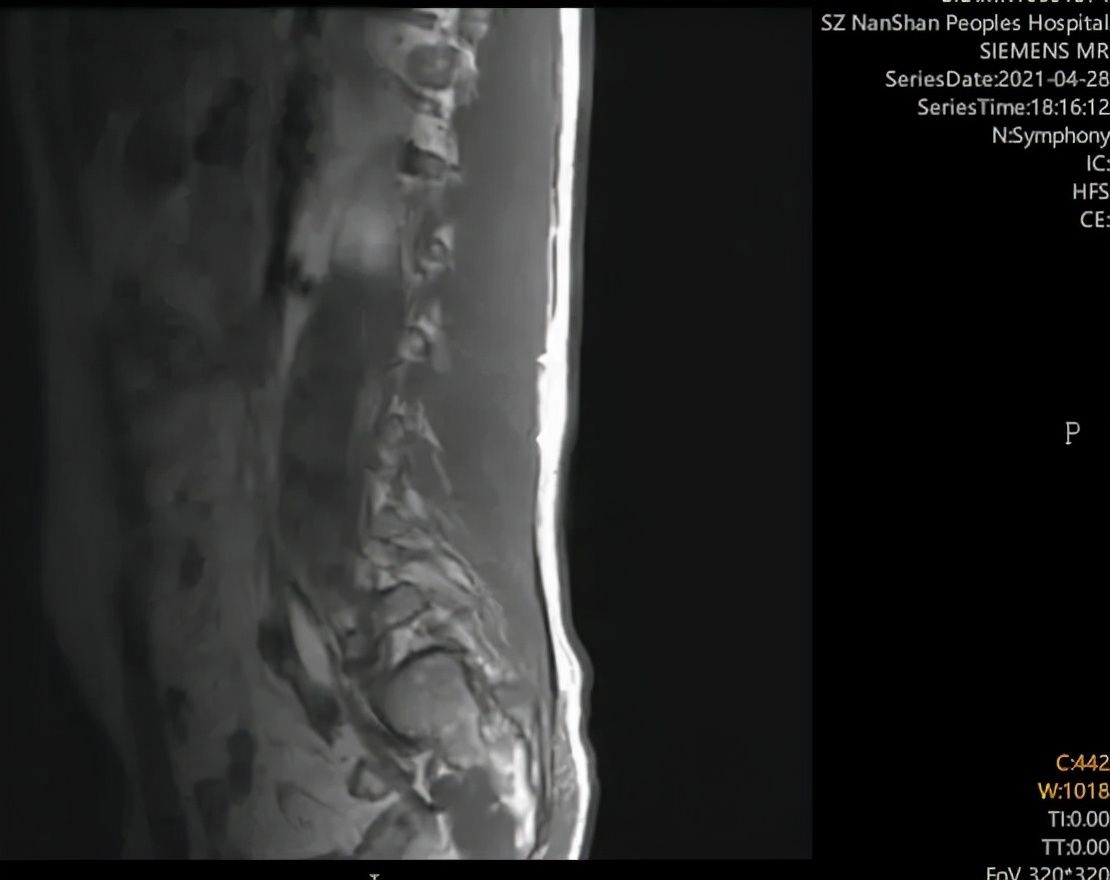

协和深圳医院影像学检查显示——

黄叔叔多处椎间盘突出、退行性变。

文章插图

疼痛科首先想到颈椎病引起的疼痛,于是被诊断为“混合型颈椎病”,并给予了相关的规范化镇痛治疗。